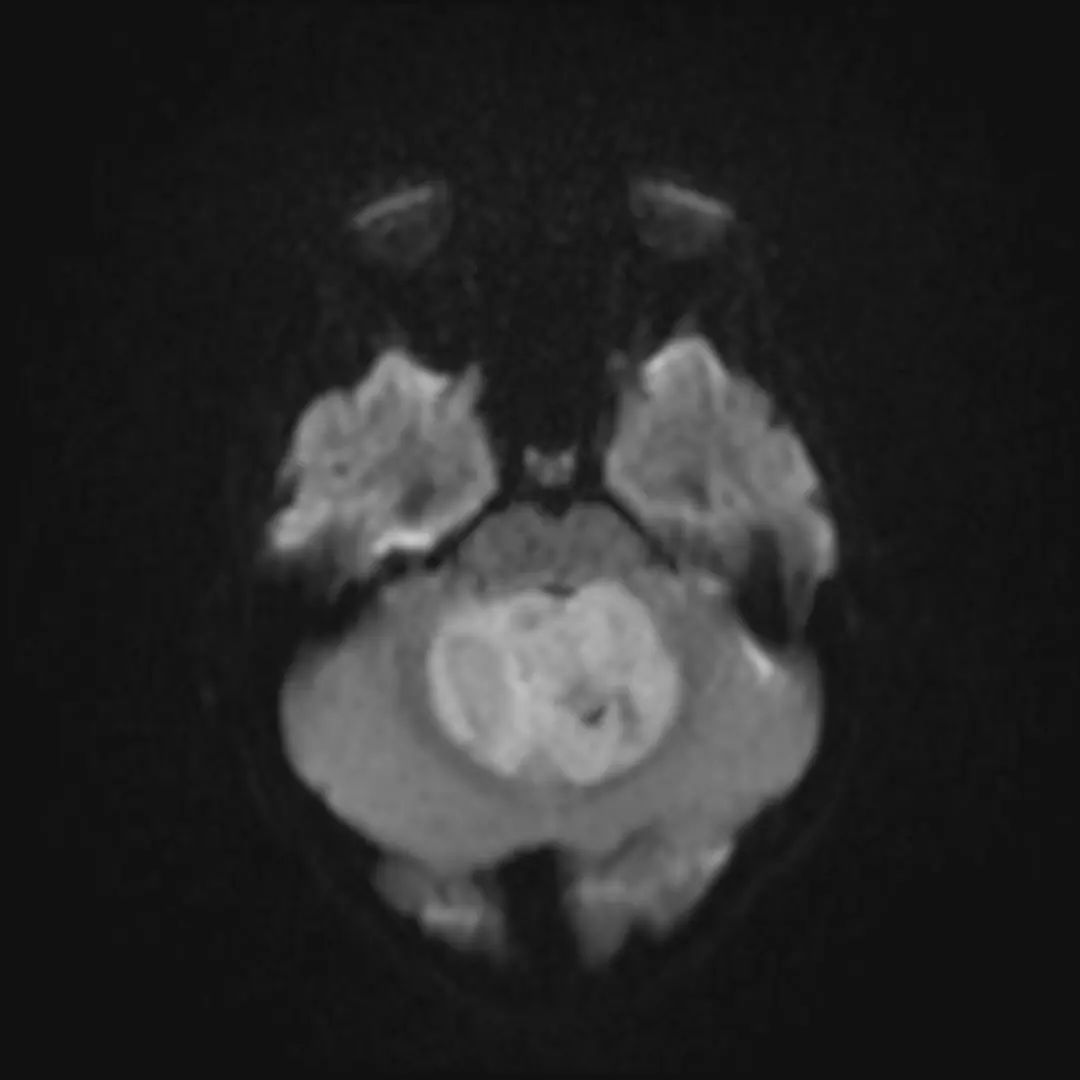

MRI表现

- T1WI:等/略低信号,T2WI上呈等/高信号。

- 边界:清晰,瘤周轻度水肿。

- 增强后:均匀强化,典型“小囊大结节”征象。

- 成人表现:MRI与CT表现均不典型。

中线小脑肿块,充满第四脑室并压迫脑干和小脑。与周围正常小脑相比,肿瘤在T1 WI上呈低信号,在T2 WI上呈轻度高信号,不均匀强化,呈囊/坏死成分,弥散受限。病理髓母细胞瘤。